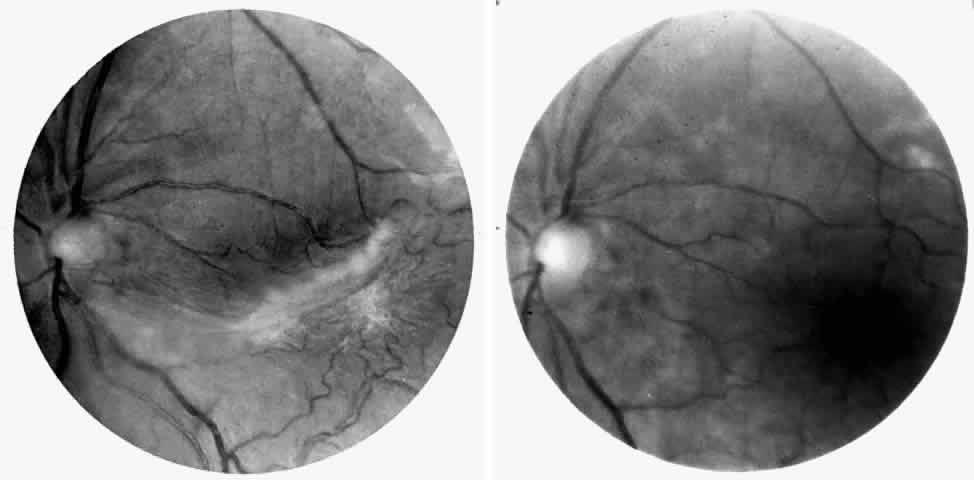

Vascular Tortuosity

Dilation and tortuosity of the retinal veins was one of the first recognized abnormalities of sickle cell eye disease. Although it is not pathognomonic of sickle cell disease, it reportedly occurs in up to 47% of patients with homozygous sickle cell anemia and 32% of patients with SC disease (Fig. 4).70 The significance of this venous tortuosity is unknown, and the incidence does not appear to be related to age.71

Fig. 4. A. Generalized vascular tortuosity, predominantly venous, in a patient with homozygous sickle cell anemia. B. Localized macular venous tortuosity in a patient with SC disease.